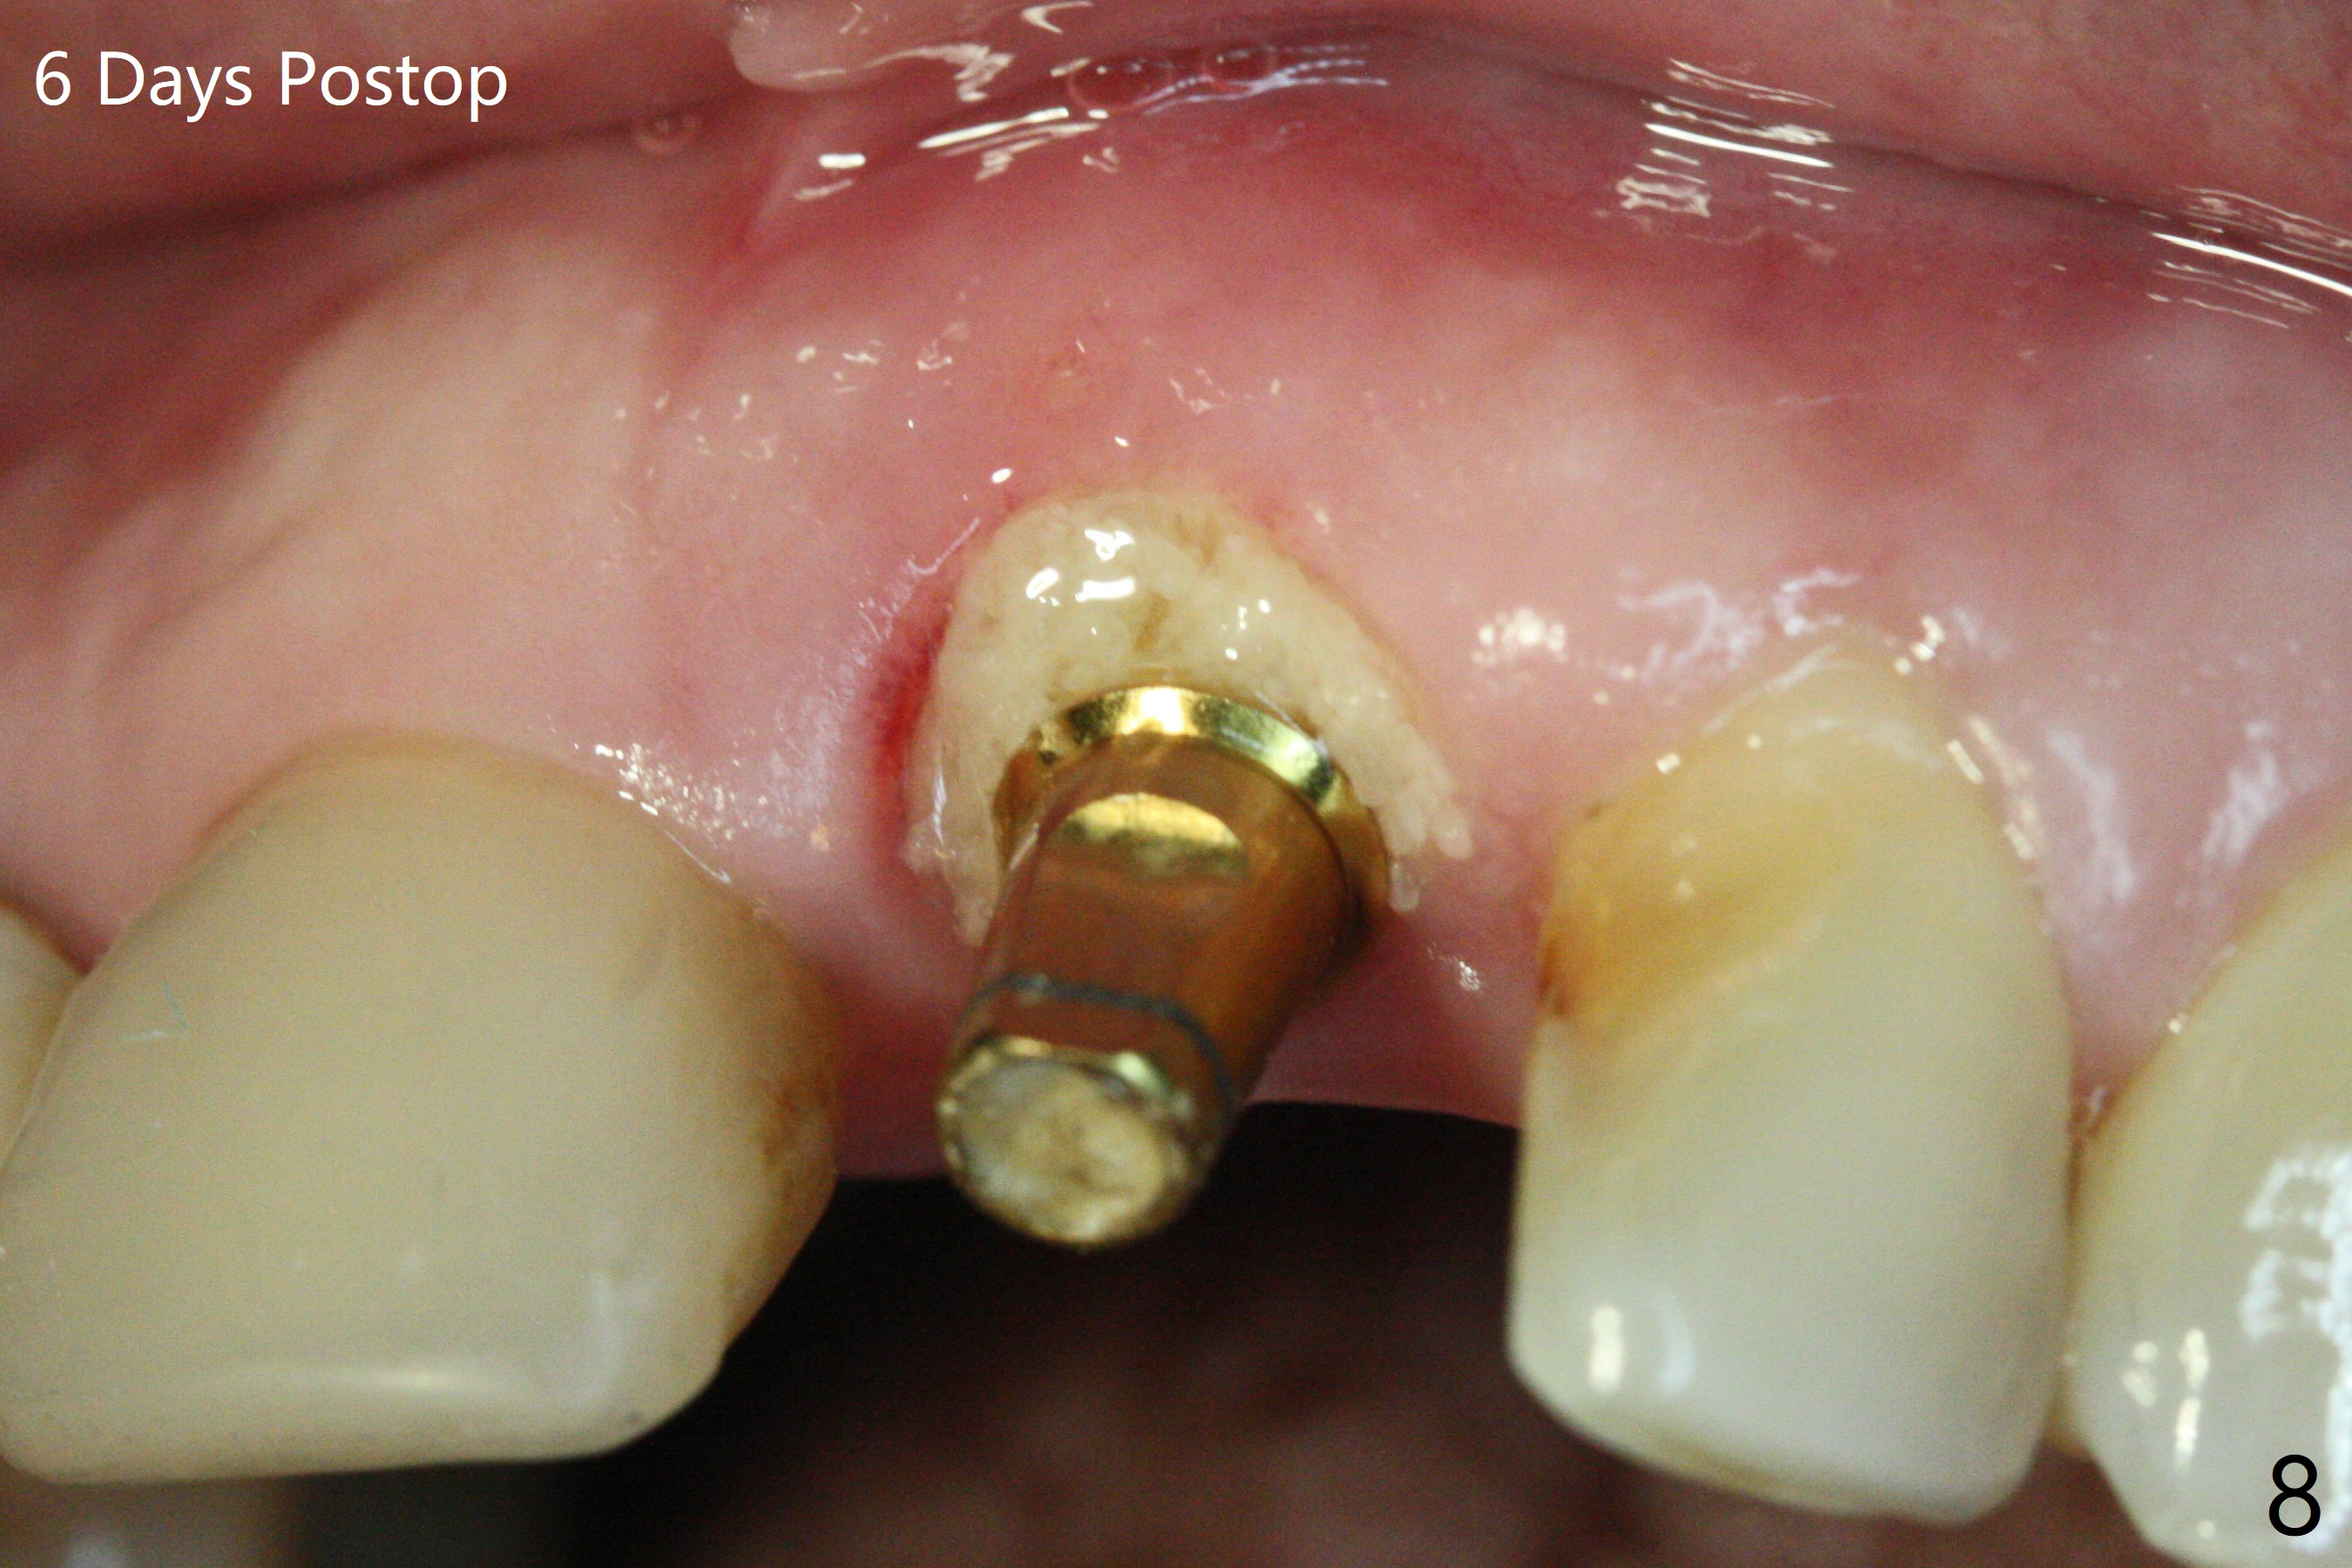

In spite of the incisobuccal shift of the tooth #9 with gingival recession (Fig.1) and loss of the buccal plate (intraop finding), there is no buccal contour collapse (Fig.2 *), due to the presence of the buccal bone of the neighboring teeth and the root of the affected tooth. After extraction, osteotomy (Fig.3) and dummy implant try in (Fig.4), a definitive implant is placed palatally with the buccal gap (Fig.5 *). In fact there is mild buccal contour collapse prior to bone graft (Fig.5 arrow). When allograft (Vera, Fig.6,7 *) is packed buccal to the implant and overlying abutment as a solid support, the buccal contour seemingly returns normal (Fig.6 arrowhead). An immediate provisional is fabricated to prevent loss of the bone graft during healing period. Bone graft kept in place by the provisional turns yellow 6 days postop (Fig.8). The buccal plate remains strong, while the fistula becomes indistinguishable. After adjustment of the provisional margin a few times (nearly 3 months postop, Fig.9,10), the gingival margin appears to have grown incisally, as compared to Fig.1. There is minimal buccal bone collapse (Fig.10). Dislodgement of the abutment and provisional forces her to return 1 year 4 months postop; the socket has healed (Fig.11). The buccal plate is not concave 1 year 4 months postop (Fig.12). The gingiva is slightly recessive (Fig.13) with mild buccal plate concavity (Fig.14) immediately before cementation. The implant could be placed ~ 1 mm deeper (Fig.15).